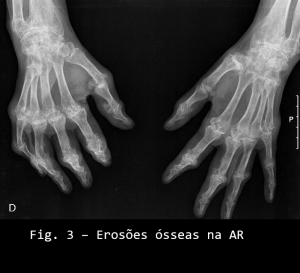

O osso é envolvido com aparecimento de erosões ósseas (visíveis ao rx) (ver figura 2 e 3) e que podem confluir e atingir grandes proporções). A presença de osteopenia é característica nos casos moderadamente avançados e nos doentes submetidos a longos períodos de terapia com corticoesteroides.